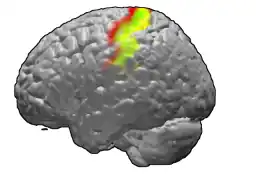

Áreas de Brodmann 3,1 e 2 no cérebro humano. A área 3 está em vermelho, área 1 em verde e área 2 em amarelo. | |

O giro pós-central é uma proeminente estrutura do lobo parietal do cérebro humano e o principal local do córtex somatossensorial primário (S1). Essa área é responsável por processar informações sensoriais táteis e proprioceptivas. No giro pós-central, existe um "mapa" sensorial chamado de homúnculo sensorial, que representa a superfície do corpo de forma distorcida, refletindo a densidade de receptores sensoriais em cada região[1]. O córtex somatossensorial foi detalhado inicialmente pelos estudos de Wilder Penfield e posteriormente refinado por pesquisas modernas, que destacaram a predominância da área de Brodmann 3 como o verdadeiro receptor das projeções talâmicas[2].